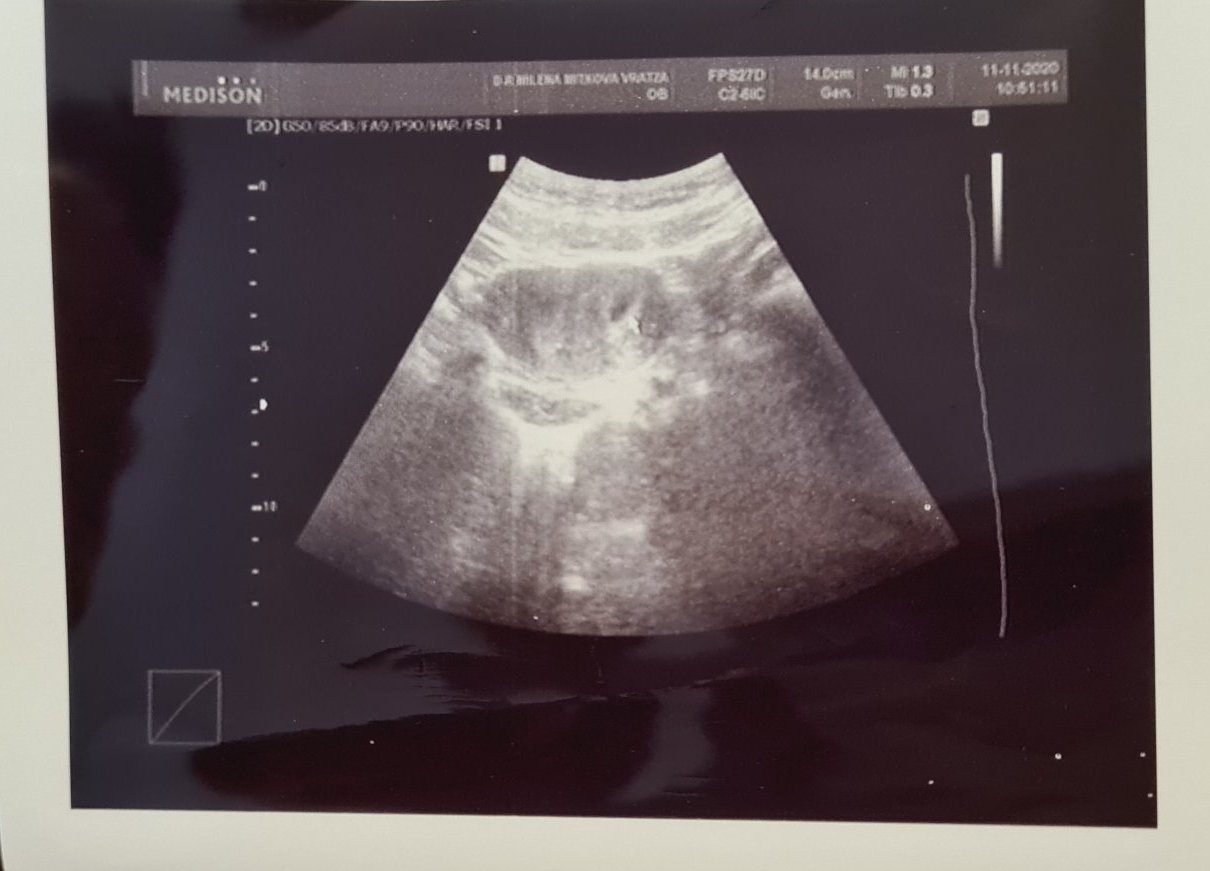

Здравейте момичета,АГ ми звънна да отида по рано днес ,прегледа ме и каза че всичко изглежда наред,бременноста си отговаря на седмиците 5+3 дни ,видяхме плодно сакче с коремен ехограф ,зацапването ми е спряло ,но продължавам с утрогестана и ми каза утре да пусна ТАТ,МАТ,FT3,FT4 и ТSX за да видим какви са стойностите. Стискайте палци прилагам и снимка от първия преглед днес